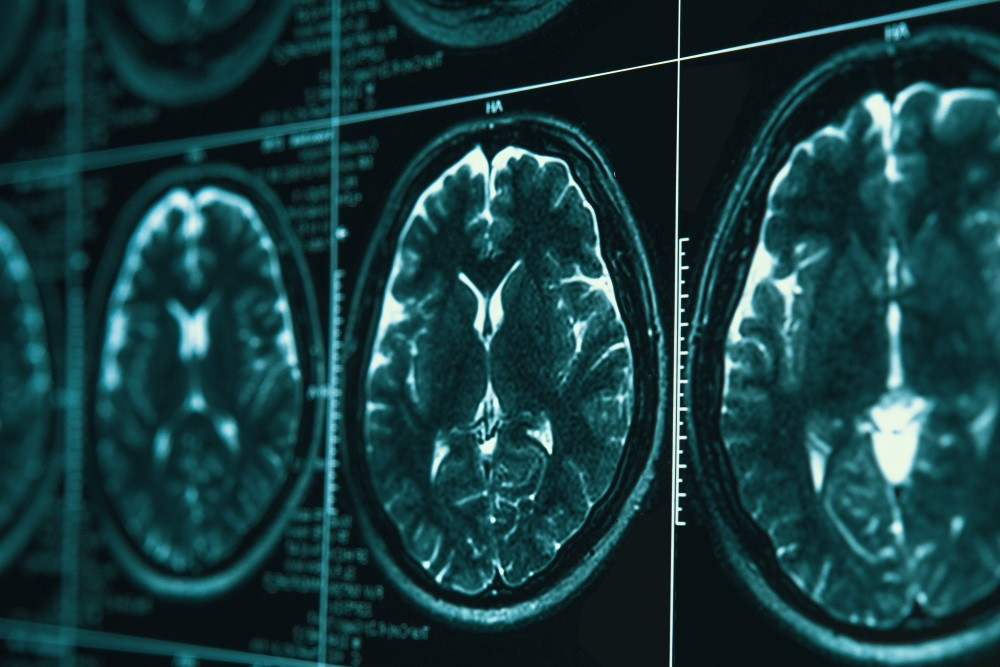

Современная медицина во многом зависит от **прогрессивных методов визуализации**, которые позволяют получить детальные изображения внутренних органов и тканей человека без инвазивных вмешательств. К таким технологиям относятся **магнитно-резонансная томография (МРТ)**, компьютерная томография (КТ), ультразвуковое исследование (УЗИ), а также различные методы радиологической диагностики. Эти методы позволяют врачу получить комплексную картину состояния пациента, выявить патологические изменения на ранних стадиях и подобрать наиболее эффективное лечение.

Одним из ключевых преимуществ современных методов визуализации является их высокая разрешающая способность и возможность визуализации в реальном времени. Например, МРТ основана на использовании сильных магнитных полей и радиоволн, что позволяет получать трёхмерные изображения тканей с высокой контрастностью без вреда для пациента. Компьютерная томография, в свою очередь, использует рентгеновское излучение для послойного сканирования, что делает ее незаменимым инструментом в диагностике травм и патологий костей и мягких тканей.